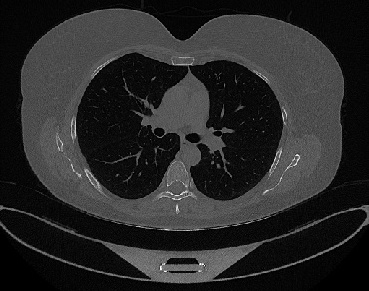

Figure 1 shows four CT scan slices, two from a non-COVID-19 CT scan, on the left and two from a COVID-19 scan, on the right. Bilateral ground glass regions are seen especially in lower lung lobes in the COVID-19 slices.